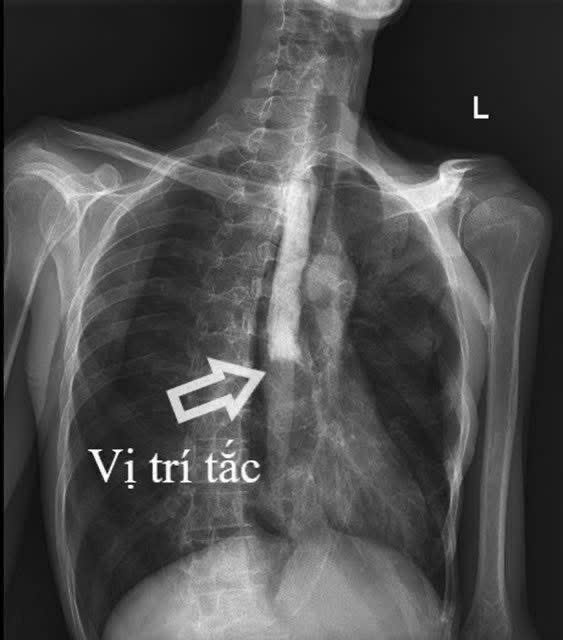

Hình ảnh vị trí bị tắc hoàn toàn thực quản đoạn 1/3 giữa.

Kết quả cận lâm sàng cho thấy bệnh nhân bị tắc hoàn toàn thực quản đoạn 1/3 giữa, kèm viêm lan tỏa dạ dày, ruột non và viêm phúc mạc. Tổn thương xuất hiện ở nhiều vị trí khiến việc xác định nguyên nhân trở nên đặc biệt khó khăn, với nhiều khả năng như lao, ung thư (lymphoma) hoặc bệnh lý tự miễn (Crohn).